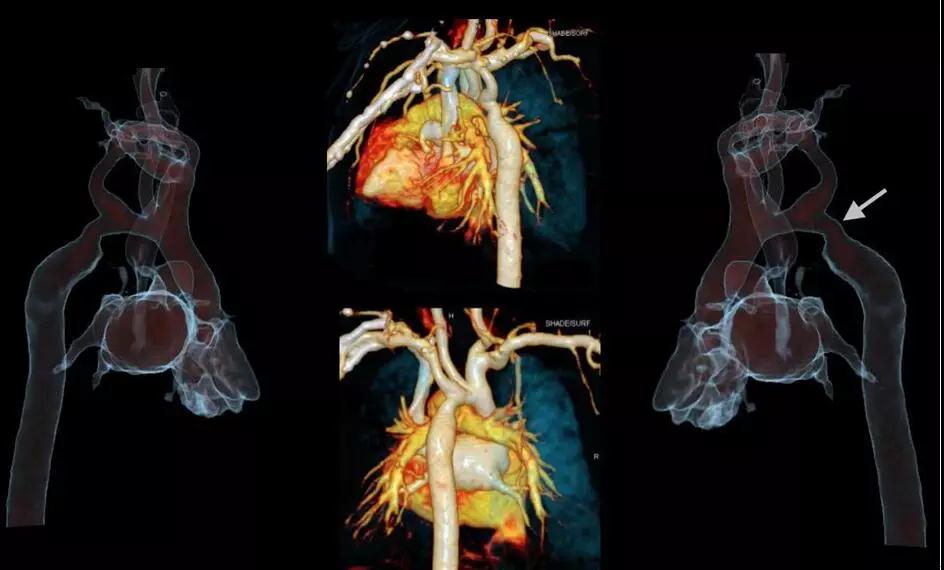

5.1秒一站式多血管同時(shí)掃描:

SOMATOMForce 開源CT的73.7厘米/秒的業(yè)內(nèi)最快掃描速度,已突破血流方向相反的成像難題,使得CTA聯(lián)合掃描在血管成像領(lǐng)域應(yīng)用研究將更加深入,未來低輻射和低對(duì)比劑量一站式多部位多血管CTA(頭頸冠脈成像、胸痛三聯(lián)征、心臟+腹部血管+下肢血管成像)將成為指導(dǎo)心臟和外周血管性疾病介入診療的重要工具。